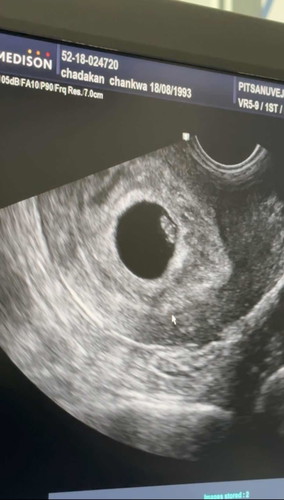

มีแม่ๆคนไหนหัวใจลูกเต้นช้าไหมคะ

6W3D ไปซาวครั้งแรก คุณหมอบอกว่า หัวใจลูกเต้นช้า 117 นัดซาวครั้งต่อ ไป ตอน 8W ถ้าเป็นแบบนี้ต่อไป ต้องทำยังไงต่อคะ หรือแม่ๆคนไหนมีประสบการ แล้วผ่านไปได้ยังไงคะ